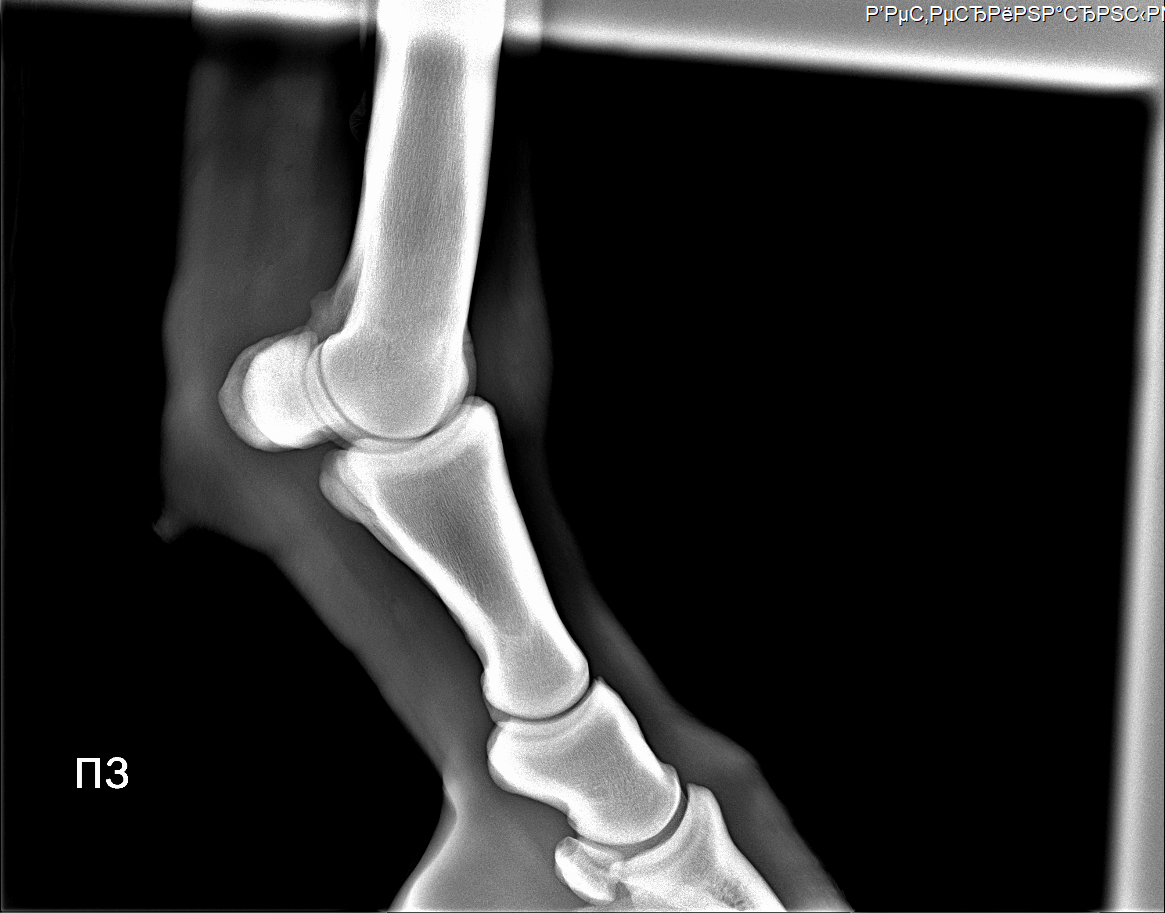

Пока шагали заметили одну интересную особенность, буквально не задолго до приезда Аркадия. Увидели что увеличился венечный сустав на задних ногах.В качестве наглядного примера сравнили ноги 2018/2019.Фото приложу.

Если быть краткой и по делу, то по приезду Аркадия провели тест, тест показал венечный ,а не скакательный сустав. По рентгену нашли артроз. Показали фото ног в сравнении, но кажется если бы не показали он бы не обратил внимания. Причина - то самое отмахивание ногами во время кормешки и попадание в стенку.